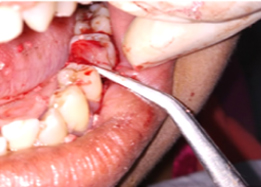

PRE OP Clinical Photograph Measuring Probing Depth